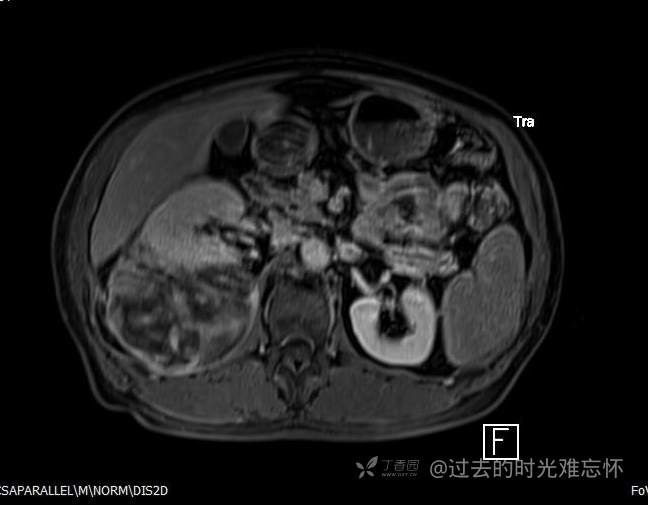

患者性别:男

患者年龄:73岁

主诉:咳嗽1月余。曾有血尿一次。后背部酸痛不适1-2年左右,无明显消瘦。

辅助检查:CT MRI

临床诊断:占位

治疗经过:手术

增强